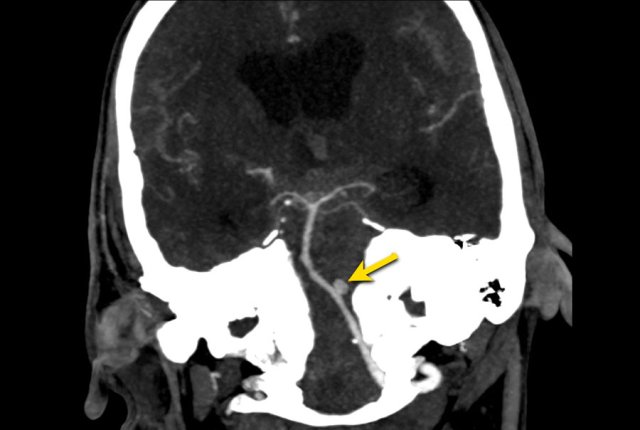

The images show a subarachnoid hemorrhage as a result of rupture of an aneurysm of the left middle cerebral artery (arrow).

The images show a subarachnoid hemorrhage from a left cerebri media aneurysm.